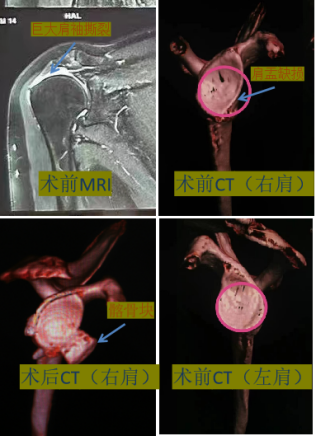

对于该肩关节不稳患者为严重肩盂骨缺损的同时合并巨大肩袖撕裂导致的软组织缺损,手术修复难度和花费较高,骨一科时志斌主任医师团队对手术方案再次进行创新改进,在肩关节镜下使用单袢钢板和带线锚钉对髂骨块进行弹性固定修补骨缺损,同时对巨大肩袖撕裂进行修补软组织缺损。术后临床效果良好,患者满意度高且降低了手术花费。经过文献查阅,此改良术式也达到了国内领先的水平。